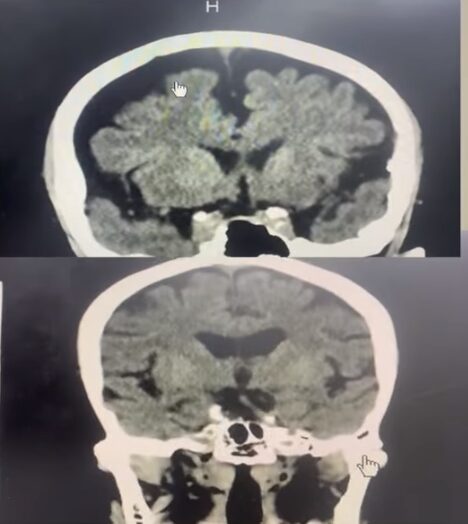

โพสต์คลิปภาพสมองของคน อายุ 66 ปี ที่สูบบุหรี่วันละซอง กับ สมองของหญิงชราวัย 90 ปี พร้อมอธิบาย ความว่า ภาพด้านบน เป็นสมองของ ชายอายุ 66 ปี ซึ่งสูบบุหรี่วันละซอง ซึ่งมีสีดำมากกว่า ยาย อายุ 90 ปี โดยสีดำที่ปรากฏนั้นคือสมองที่ฝ่อ ทำให้ความจำแย่มาก แตกต่างจาก ยาย 90 ปี ที่มีเนื้อสมองมากกว่า

ด้านบนสมองคนสูบบุหรี่วันละซอง ด้านล่าง สมองยายวัย 90 ปี